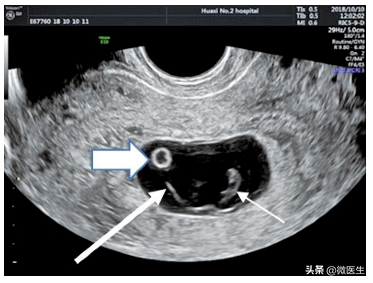

(1)妊娠囊超声显示最早期的妊娠囊为极小的圆形无回声区,周边为发育的绒毛形成的均勺高回声环。随着妊娠进展,绒毛与子宫蜕膜形成特征性的“双环征”(下图)。经腹部超声在孕5~6周发现,经腔内超声在孕4~5周发现。

孕38天,经腔内超声检查显示“双环征”(粗箭头)、孕囊、卵黄囊(长箭头)及胎芽(细箭头)随着孕周増加。

妊娠囊可为椭圆形、不规则形等需与假妊娠囊(宫腔积液)鉴别,宫腔积液无“双环征”,形态与宫腔一致,位于宫腔中央,周边强回声为分离的子宫内膜。